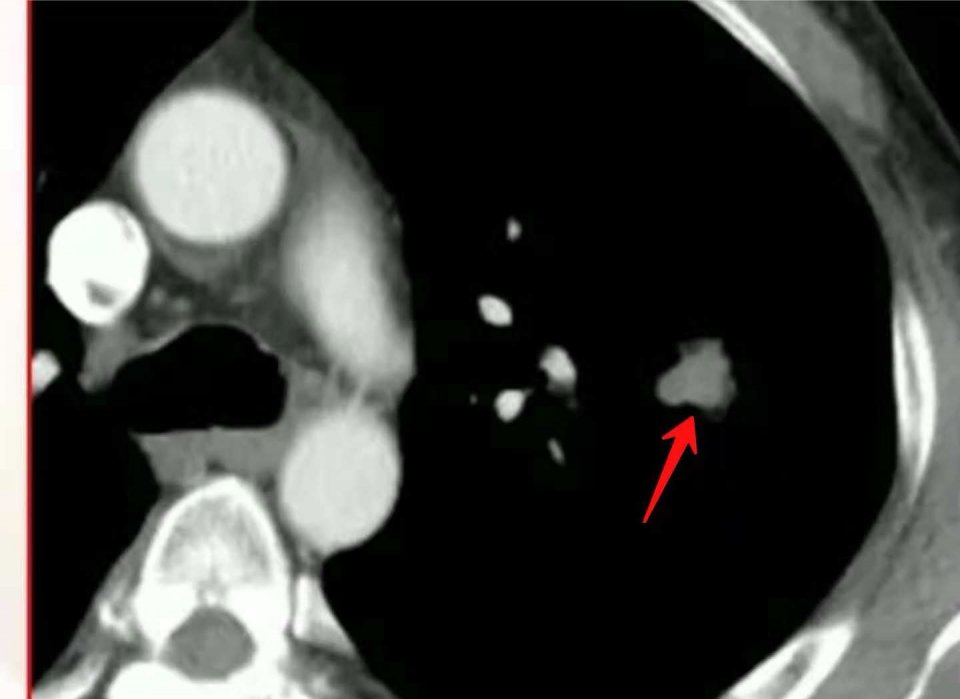

像这位病人,反复胸闷两个月,小细胞肺癌并广泛转移。

化疗两个周期后复查,病灶显著缩小: